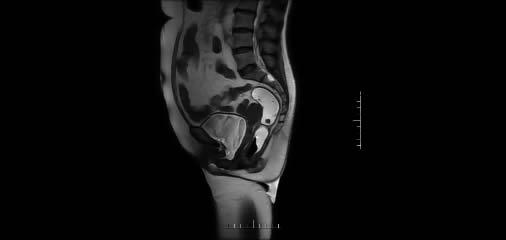

電(diàn)影序列實時捕捉盆底器官運動狀態,精準分級脫垂(chuí)程度(如(rú)膀(bǎng)胱、子宮脫垂)

上圖為一例(lì)膀胱‖度脫垂,子宮|度脫垂患者,MRI動態圖像,可顯(xiǎn)示膀胱及(jí)子宮脫垂,並(bìng)對脫垂進(jìn)行分級。